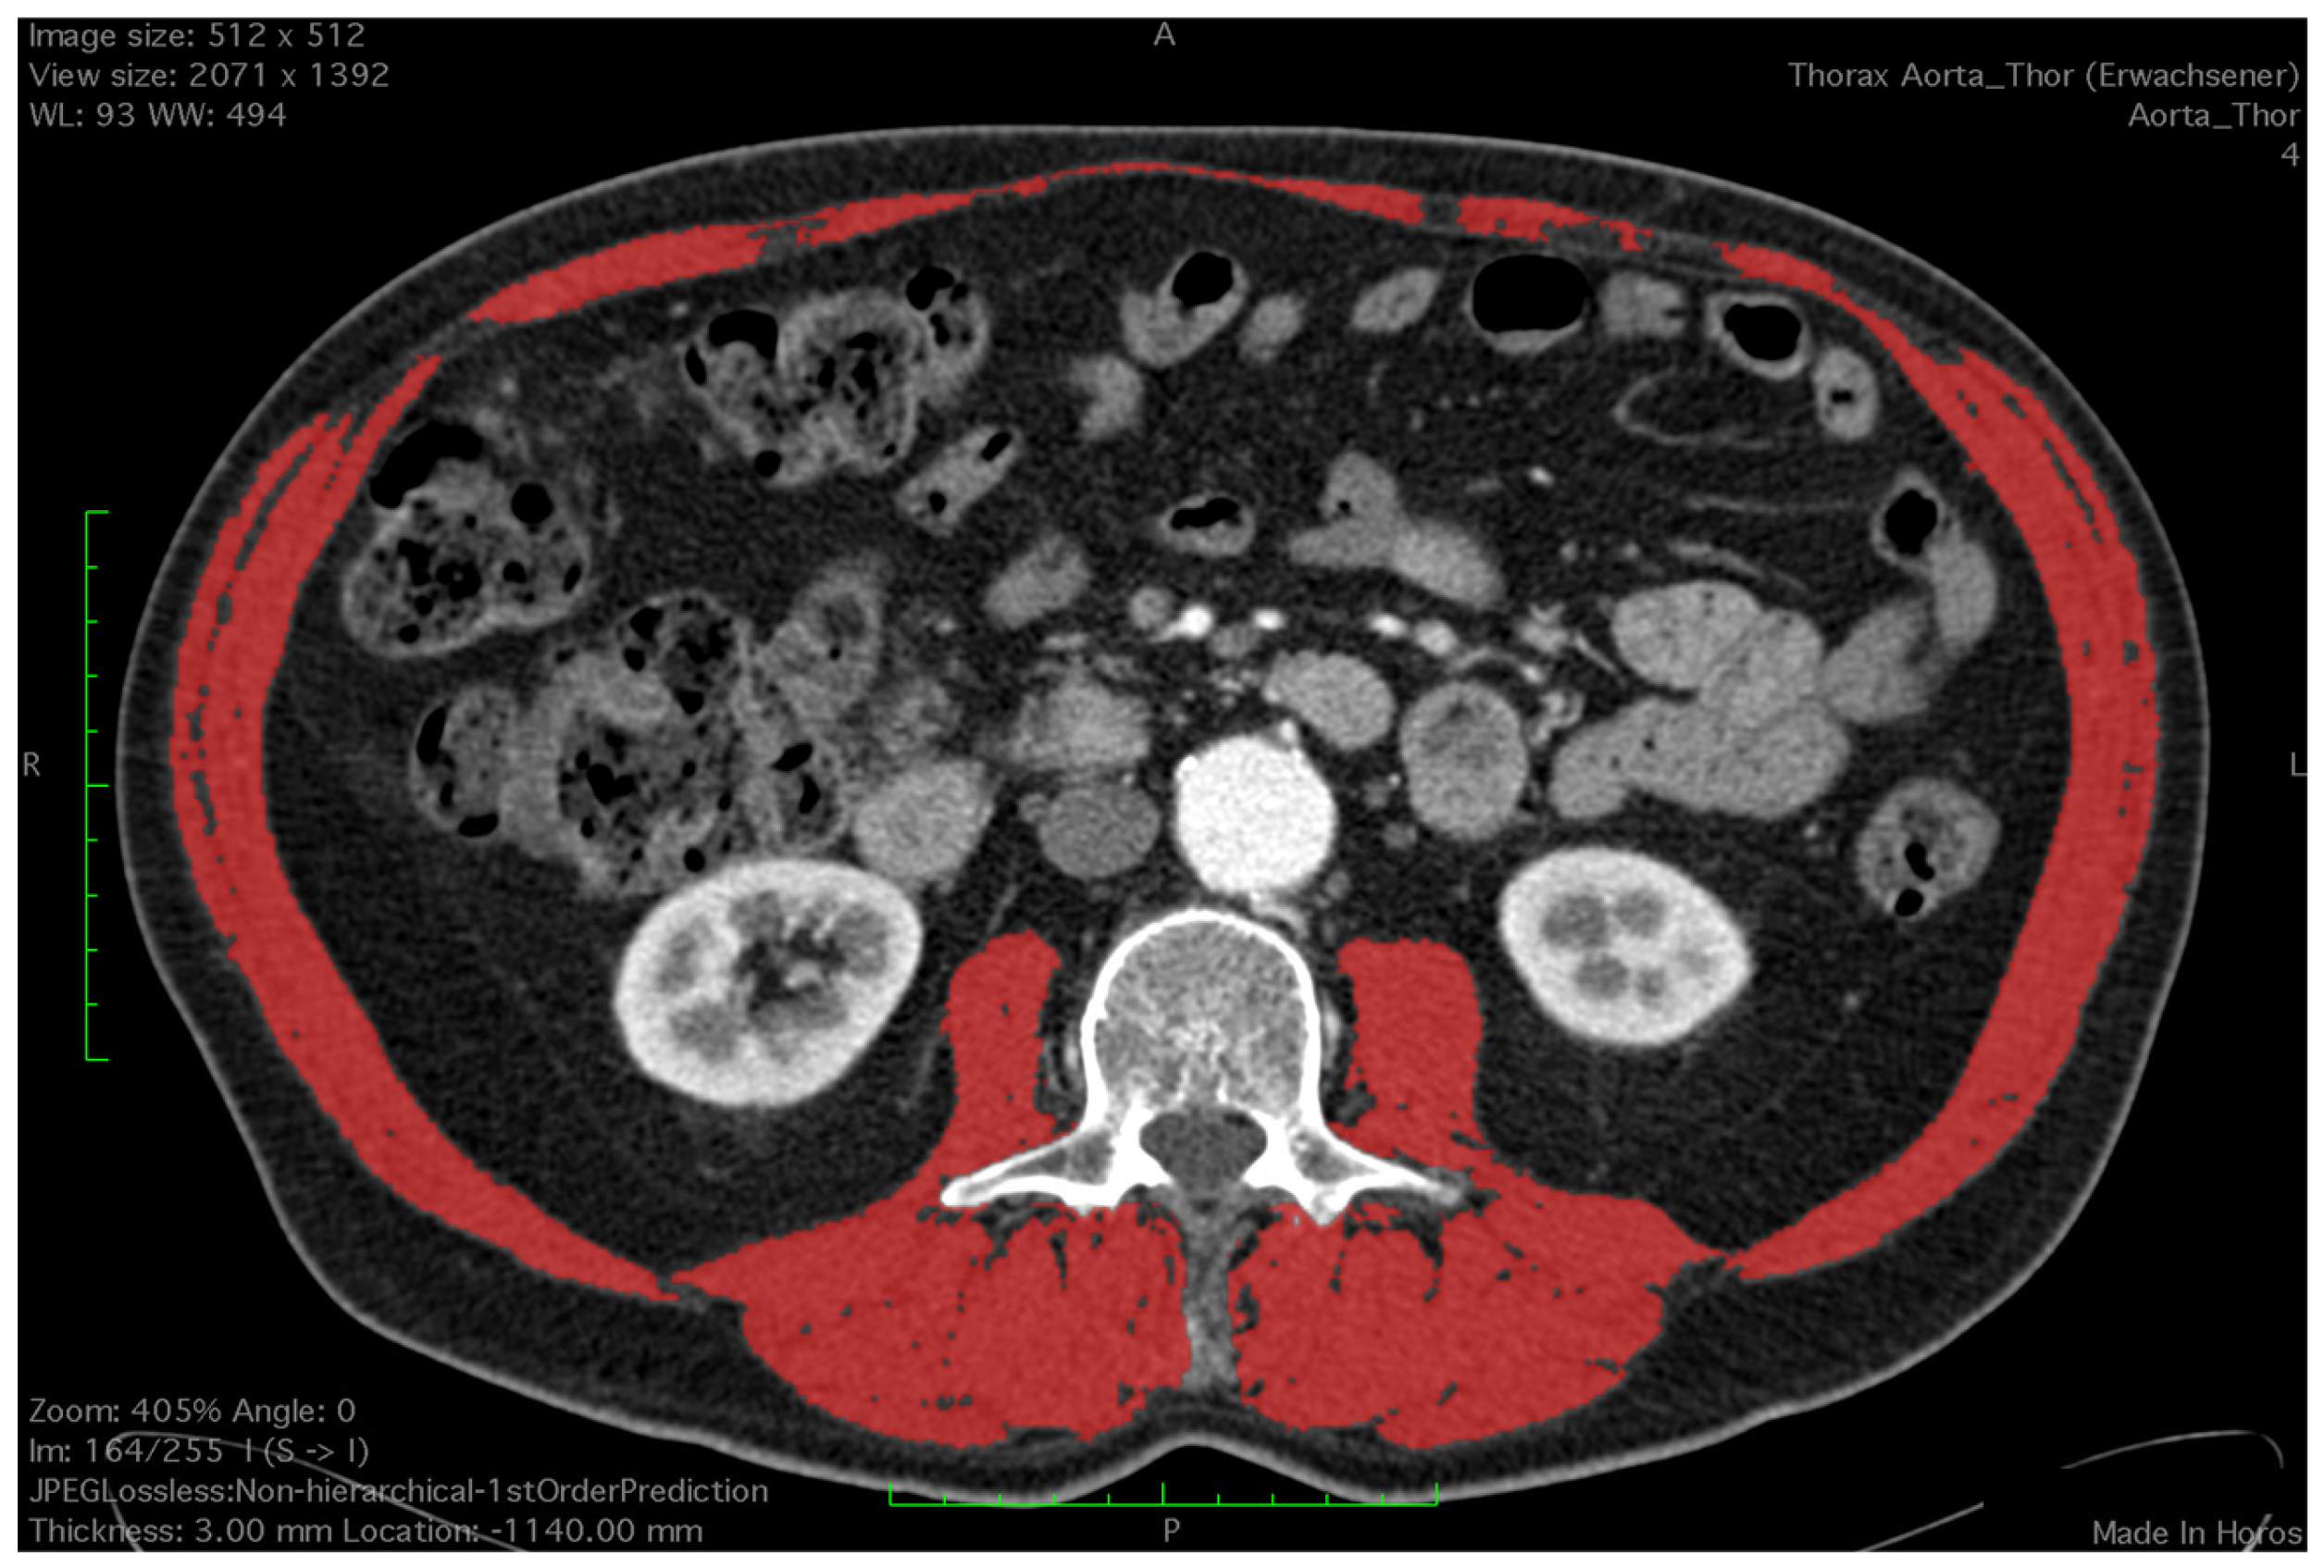

2.2. Assessment of Skeletal Muscle

- Mourtzakis, M.; Prado, C.; Lieffers, J.; Reinman, T.; McCargar, L.; Baracos, V.E. A practical and precise approach to quantification of body composition in cancer patients using computed tomography images acquired during routine care. Appl. Physiol. Nutr. Metab. 2008, 33, 997–1006. [Google Scholar] [CrossRef] [PubMed]

- Shen, W.; Punyanitya, M.; Wang, Z.; Gallagher, D.; St.-Onge, M.-P.; Albu, J.; Heymsfield, S.B.; Heshka, S. Total body skeletal muscle and adipose tissue volumes: Estimation from a single abdominal cross-sectional image. J. Appl. Phsyiol. 2004, 97, 2333–2338. [Google Scholar] [CrossRef] [PubMed]